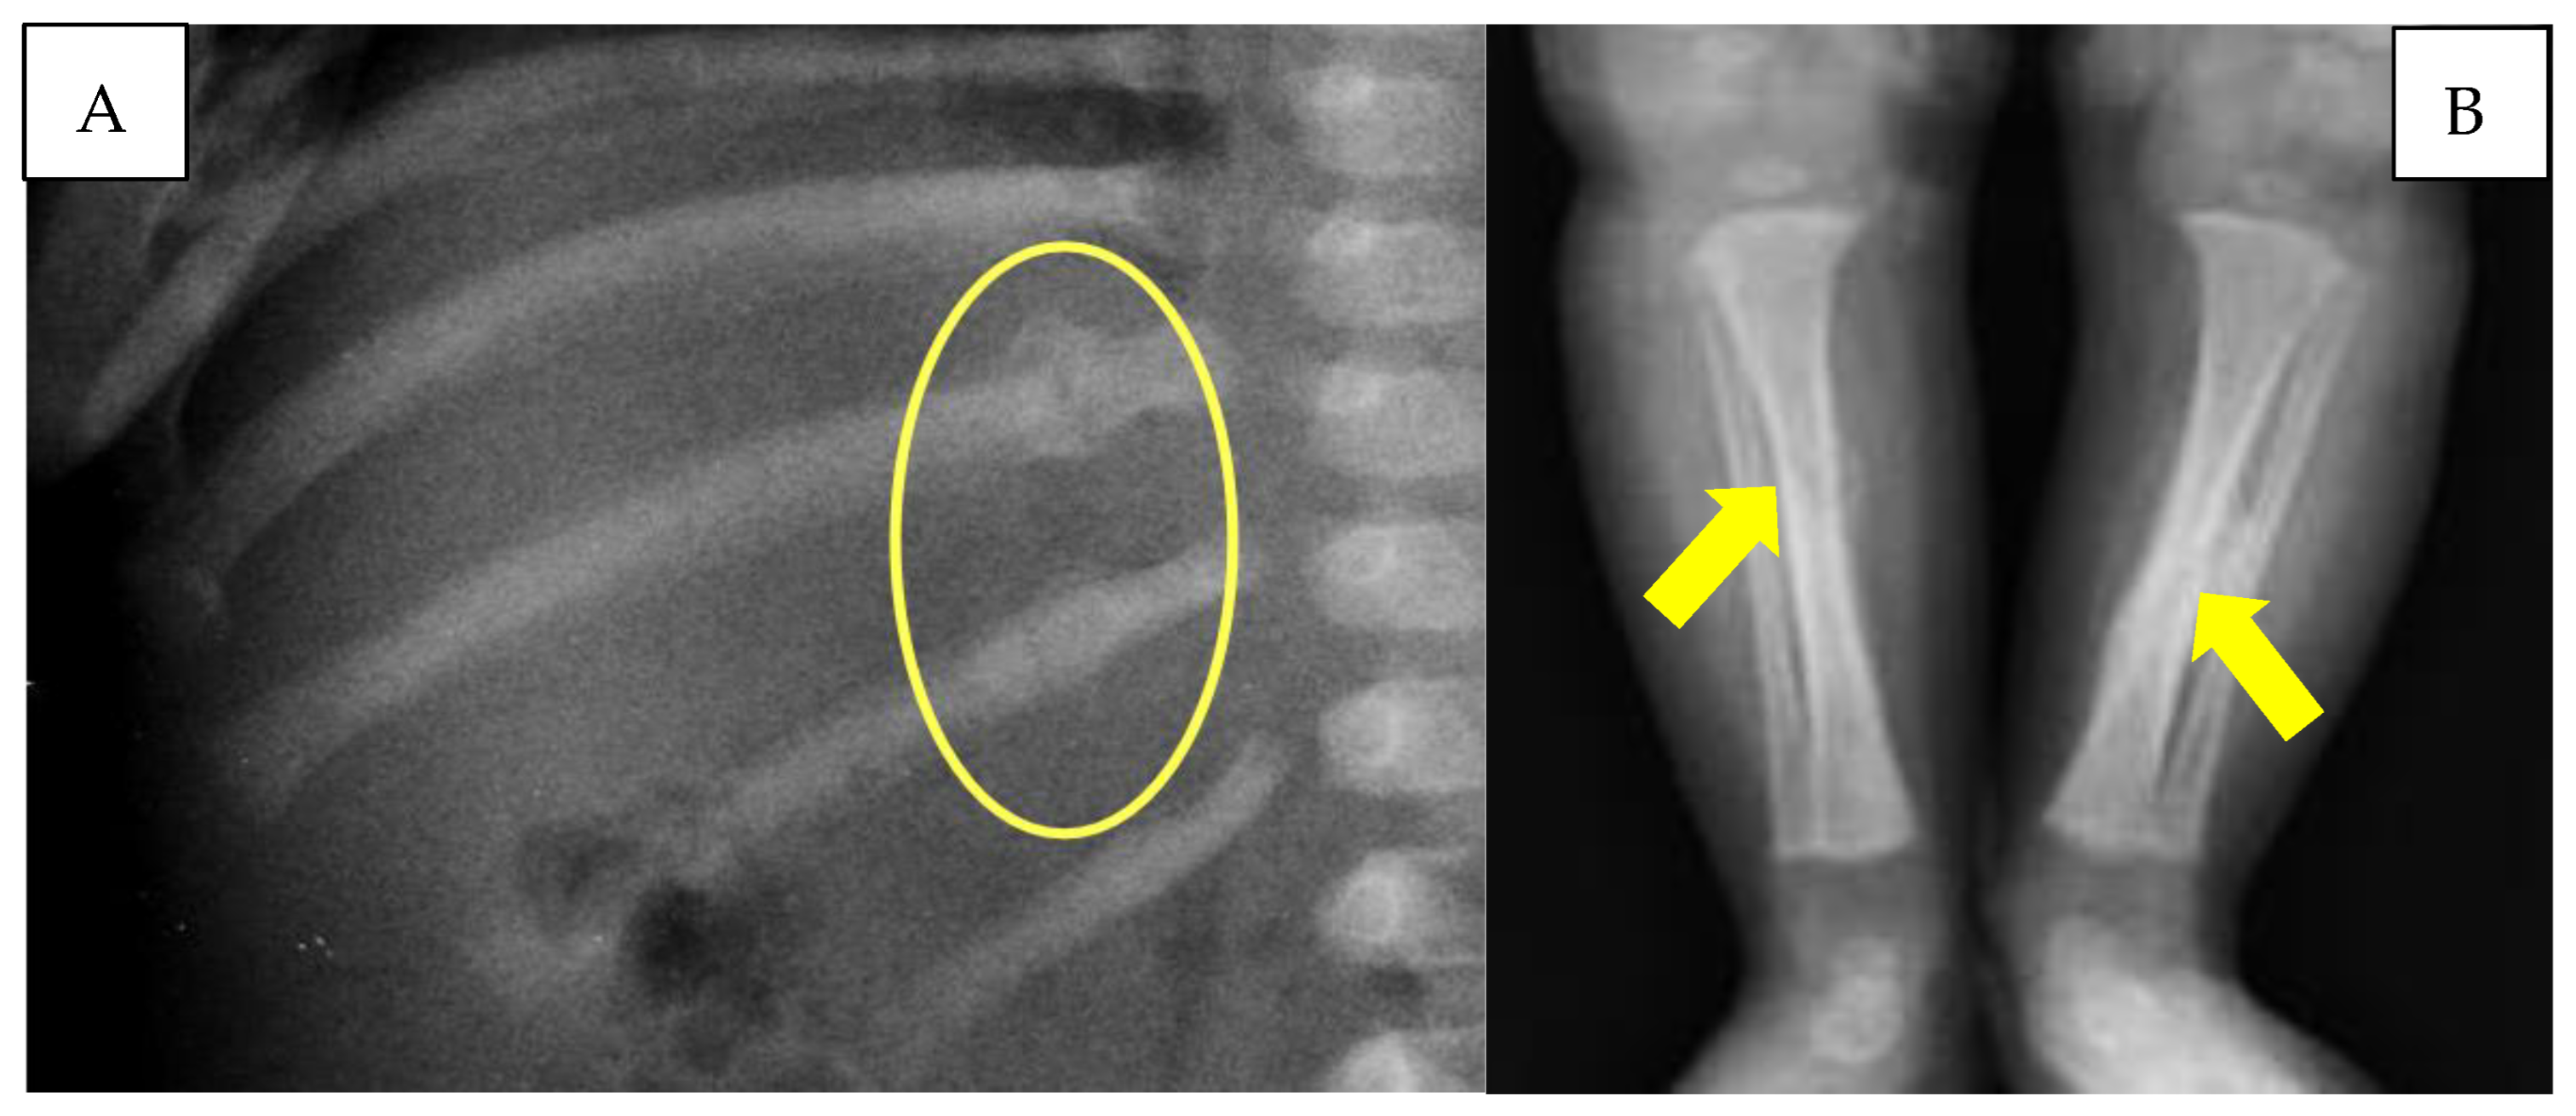

The infant also underwent a chest X-ray, which showed the presence of multiple rib fractures and a left clavicular fracture. The lower limb X-ray documented the presence of a tibial diaphyseal spiral fracture bilaterally undergoing ossification, with the presence of bony callus more significant on the left tibia (Figure 4).

(A) Rib fractures with reparative phenomena (yellow circle). (B) Diaphyseal tibial spiral fractures (yellow arrows).

On the other hand, with regard to the spiral fractures of the tibiae and the multiple costal fractures, the presence of bone callus on radiographic images made it possible to define the lesions as non-coincident with cranio-encephalic trauma. In particular, the tibial fractures, due to the particular spiral conformation, were not correlated with direct traumatism but due to a mechanism of extreme rotation of each lower limb. The detected rib fractures, located at the level of the posterior arch of two adjacent ribs, are also typically frequent in cases of child abuse [38]. For all these reasons, the authors identify the pathogenetic mechanism on the basis of the head injury observed in the child as a case of ‘Compressed Baby Head’ (Figure 7).